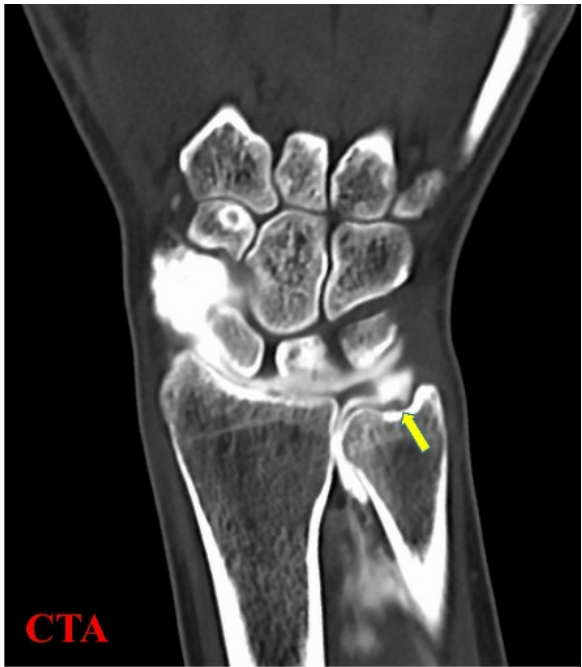

참고로 TFCC 손상을

확실하게 진단하는 검사법은

'초음파'가 아니라

**'MRI 관절 조영술'입니다.